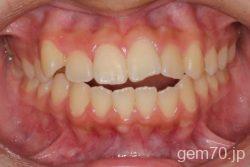

症状:開咬装置:セラミックブラケット | 抜歯世代:10代 | 高校生

主訴)前歯がかみ合わない

診断)開咬

年齢)18歳

使用装置)マルチブラケット装置

治療方法)抜歯 4|4/4|4

治療期間) 2年4ヵ月 通院回数 27回